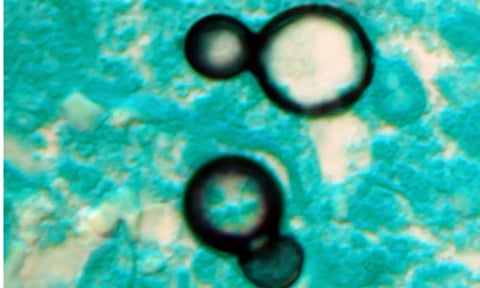

The study, led by scientists at the universities of Manchester in the UK, Amsterdam, and the Westerdijk Institute in the Netherlands, showed that most fungal pathogens identified by the World Health Organisation (WHO) are either already resistant or rapidly acquiring resistance to antifungal drugs.

Aspergillus, Candida, Nakaseomyces glabratus, and Trichophyton indotineae are the major fungicide resistant infections. These can have devastating health impacts on the elderly and people with weak immune systems.